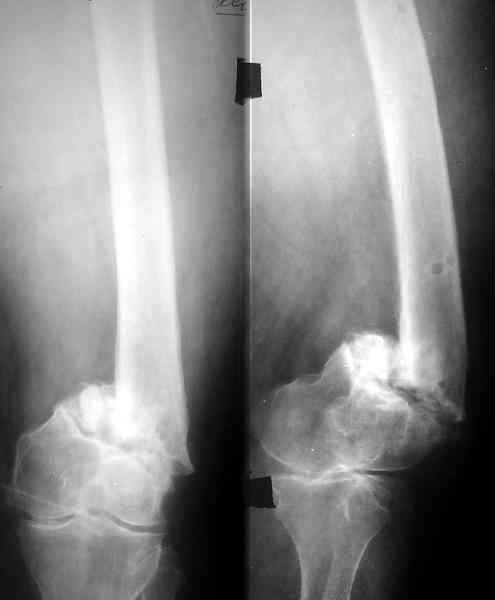

Доброго времени суток,уважаемые коллеги! Прошу вашего мнения. Больная, 53 лет,поступила с диагнозом: Ложный сустав н/3 бедренной кости слева. Травма в 1995г. Закрытый перелом н/3 левого бедра,лечение скелетным вытяжением. 15 лет ходила без трости. В 1-2010 года, рефрактура левого бедра в н/3. Лечение консервативное, скелетное вытяжение 2,5 месяца. Выписана в полужестком туторе. На ногу не опиралась, передвигается при помощи костылей. Инвалид 3 гр. посттромбофлебитический синдром левой нижней конечности. По дуплексному сканированию сосудов нижних конечностей вены проходимы, только на голени подкожная вена "посттромбофлебитическая".Из сопутствующих: ГБ,ДУЗ 0ст.Ожирение 1 ст.Предлагается костная пластика одним из существующих методов, накостный синтез мыщелковой пластиной LSP (Synthez). Укорочение левой ноги 3,5 см. Есть опасение, что накостный синтез ограничит периостальную регенерацию, да и травматичность операции при сопутствующих заболеваниях опасна в плане осложнений. Хотелось бы узнать мнение о ЧКДО и интрамедуллярном синтезе у данной пациентки. Стоит ли сначала "срастить" перелом, а потом коррегировать длину конечности? Или это нужно делать сразу? Может быть вообще ничего не делать и разрешить нагрузку? Пробую приложить Rn-гр. и томогр. Извиняюсь за качество обработки. Спасибо. Надеюсь на ваше понимание.

Смещение по длине см на 3 видно на снимке. Удобно и нетравматично восстановить длину и устранить смещение по ширине аппаратом.